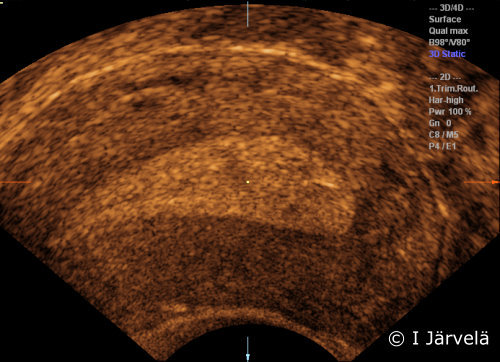

Endometrium in the secretory phase (ultrasound scan). In the secretory phase, progesterone makes the endometrium appear lighter (more echogenic) on US compared to the surrounding myometrium but no longer increases the thickness of the endometrium.

Picture: Ilkka Järvelä; text: Dimitrios Scordas